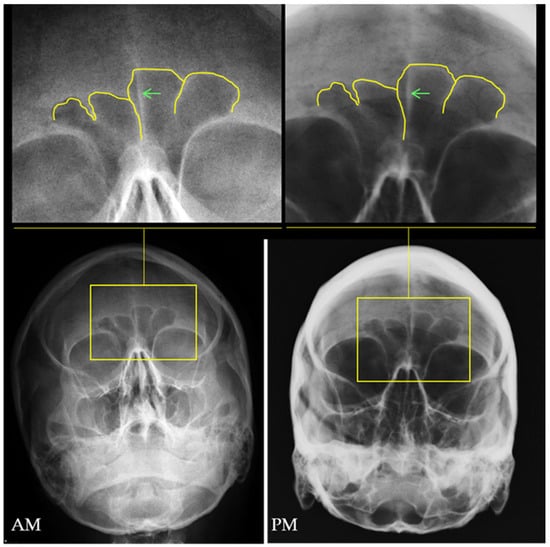

The frontal sinus has been extensively researched as an individualizing structure, presenting unique architecture that differs even in monozygotic twins [33,34,35,36]. Its morphological variation ranges from minimal expression (or even aplasia) to complex labyrinthic formations, presenting variation in the presence or absence and asymmetry of right and left lobes, sinus outline morphology, and number and location of septa [37,38]. In the first author’s experience, the location and morphology of the crista galli of the ethmoid and the frontal sinus lobes, are informative structures that can add to the comparisons (Figure 4), but in order to use the crista galli in the comparison, the PM image should mimic in high detail the AM in terms of projection and positioning of the cranium. Moreover, the anatomical variations of the frontal sinus aren’t significantly influenced by sex or population affinity [38], and the highly individualistic morphology generally supersedes more subtle differences related to imaging orientation or image quality concerns [37], giving this structure great value for personal identification in forensic casework (Figure 5).

Figure 4. Frontal sinus comparison between an antemortem (AM) Waters projection and a postmortem (PM) radiograph of the cranium in similar orientation. The frontal sinus outline and septa are highlighted in yellow and the crista galli is indicated by the green arrow in the superior images. Source: Department of Applied Forensic Sciences at Mercyhurst University casework.